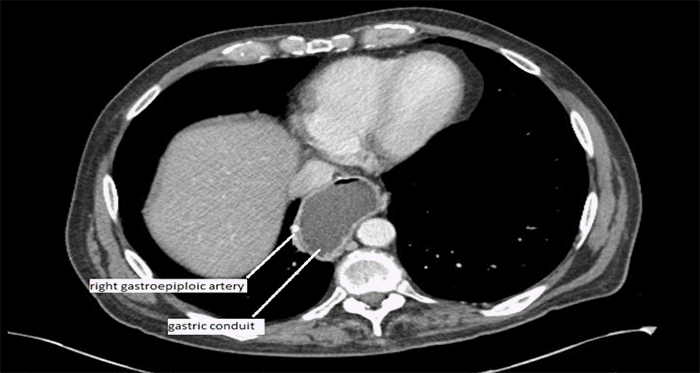

Following a clinic discussion, the patient opted for surgical resection of the ampullary lesion. Preoperative angiography (Figure 2) delineated the gastric conduit’s vasculature, confirming exclusive reliance on the right gastroepiploic artery and demonstrating no contributions from the SMA or short gastric arteries, as suggested by prior axial imaging (Figure 3). The patient completed a bowel prep the evening before surgery, allowing for the possibility of colonic interposition.

Figure 3. Preoperative CT Scan (axial view). Published with Permission

Gastric conduit vascularized by the right gastroepiploic artery